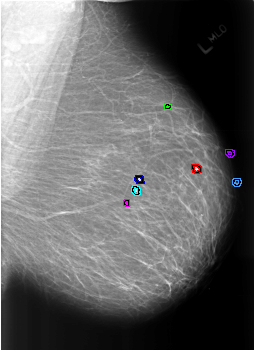

B_3177_1.LEFT_MLO

LEFT_MLO LINES 5592 PIXELS_PER_LINE 4064 BITS_PER_PIXEL 12 RESOLUTION 50 OVERLAY

FILE: B_3177_1.LEFT_MLO.OVERLAY

TOTAL_ABNORMALITIES 7

ABNORMALITY 1

LESION_TYPE CALCIFICATION TYPE EGGSHELL DISTRIBUTION N/A

ASSESSMENT 2

SUBTLETY 5

PATHOLOGY BENIGN_WITHOUT_CALLBACK

ABNORMALITY 2

LESION_TYPE CALCIFICATION TYPE LUCENT_CENTER DISTRIBUTION N/A

ABNORMALITY 3

ABNORMALITY 4

ABNORMALITY 5

ABNORMALITY 6

ABNORMALITY 7